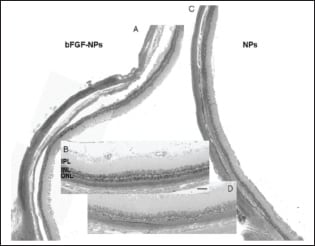

Sakai et al.19 prepared ~585-nm–diameter basic fibroblast growth factor (bFGF) nanoparticles using bovine gelatin and recombinant human bFGF. Eight weeks after intravitreal injection into RCS rat eyes, bFGF nanoparticles were still present in the outer retina. Compared to an intravitreal injection of 2.5 µg bFGF, bFGF nanoparticle–treated animals had better outer nuclear layer preservation and better-preserved electroretinograms (Figures 1 and 2).

Figure 1. Morphologic rescue of the superior retina of RCS rats. Representative photographs eight weeks after injection with bFGF-nanoparticles (NPs) (A, B) and blank NPs (C, D). Note the preservation of the outer nuclear layer (ONL) in the bFGF-NP–treated retina, compared with the blank NP-treated retina. Higher magnification showed the respective differences better. Original magnification, x100. Scale bar, 50 ∞m. Reproduced with permission from Sakai et al.19